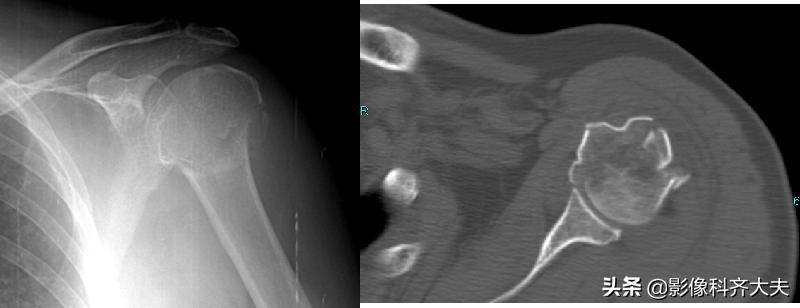

肱骨骨折

应用于解剖复杂部位

骨盆、髋、肩、膝、面骨、脊柱

了解有无骨折、骨折片的数目和位置

三位重建可立体显示骨折的详情